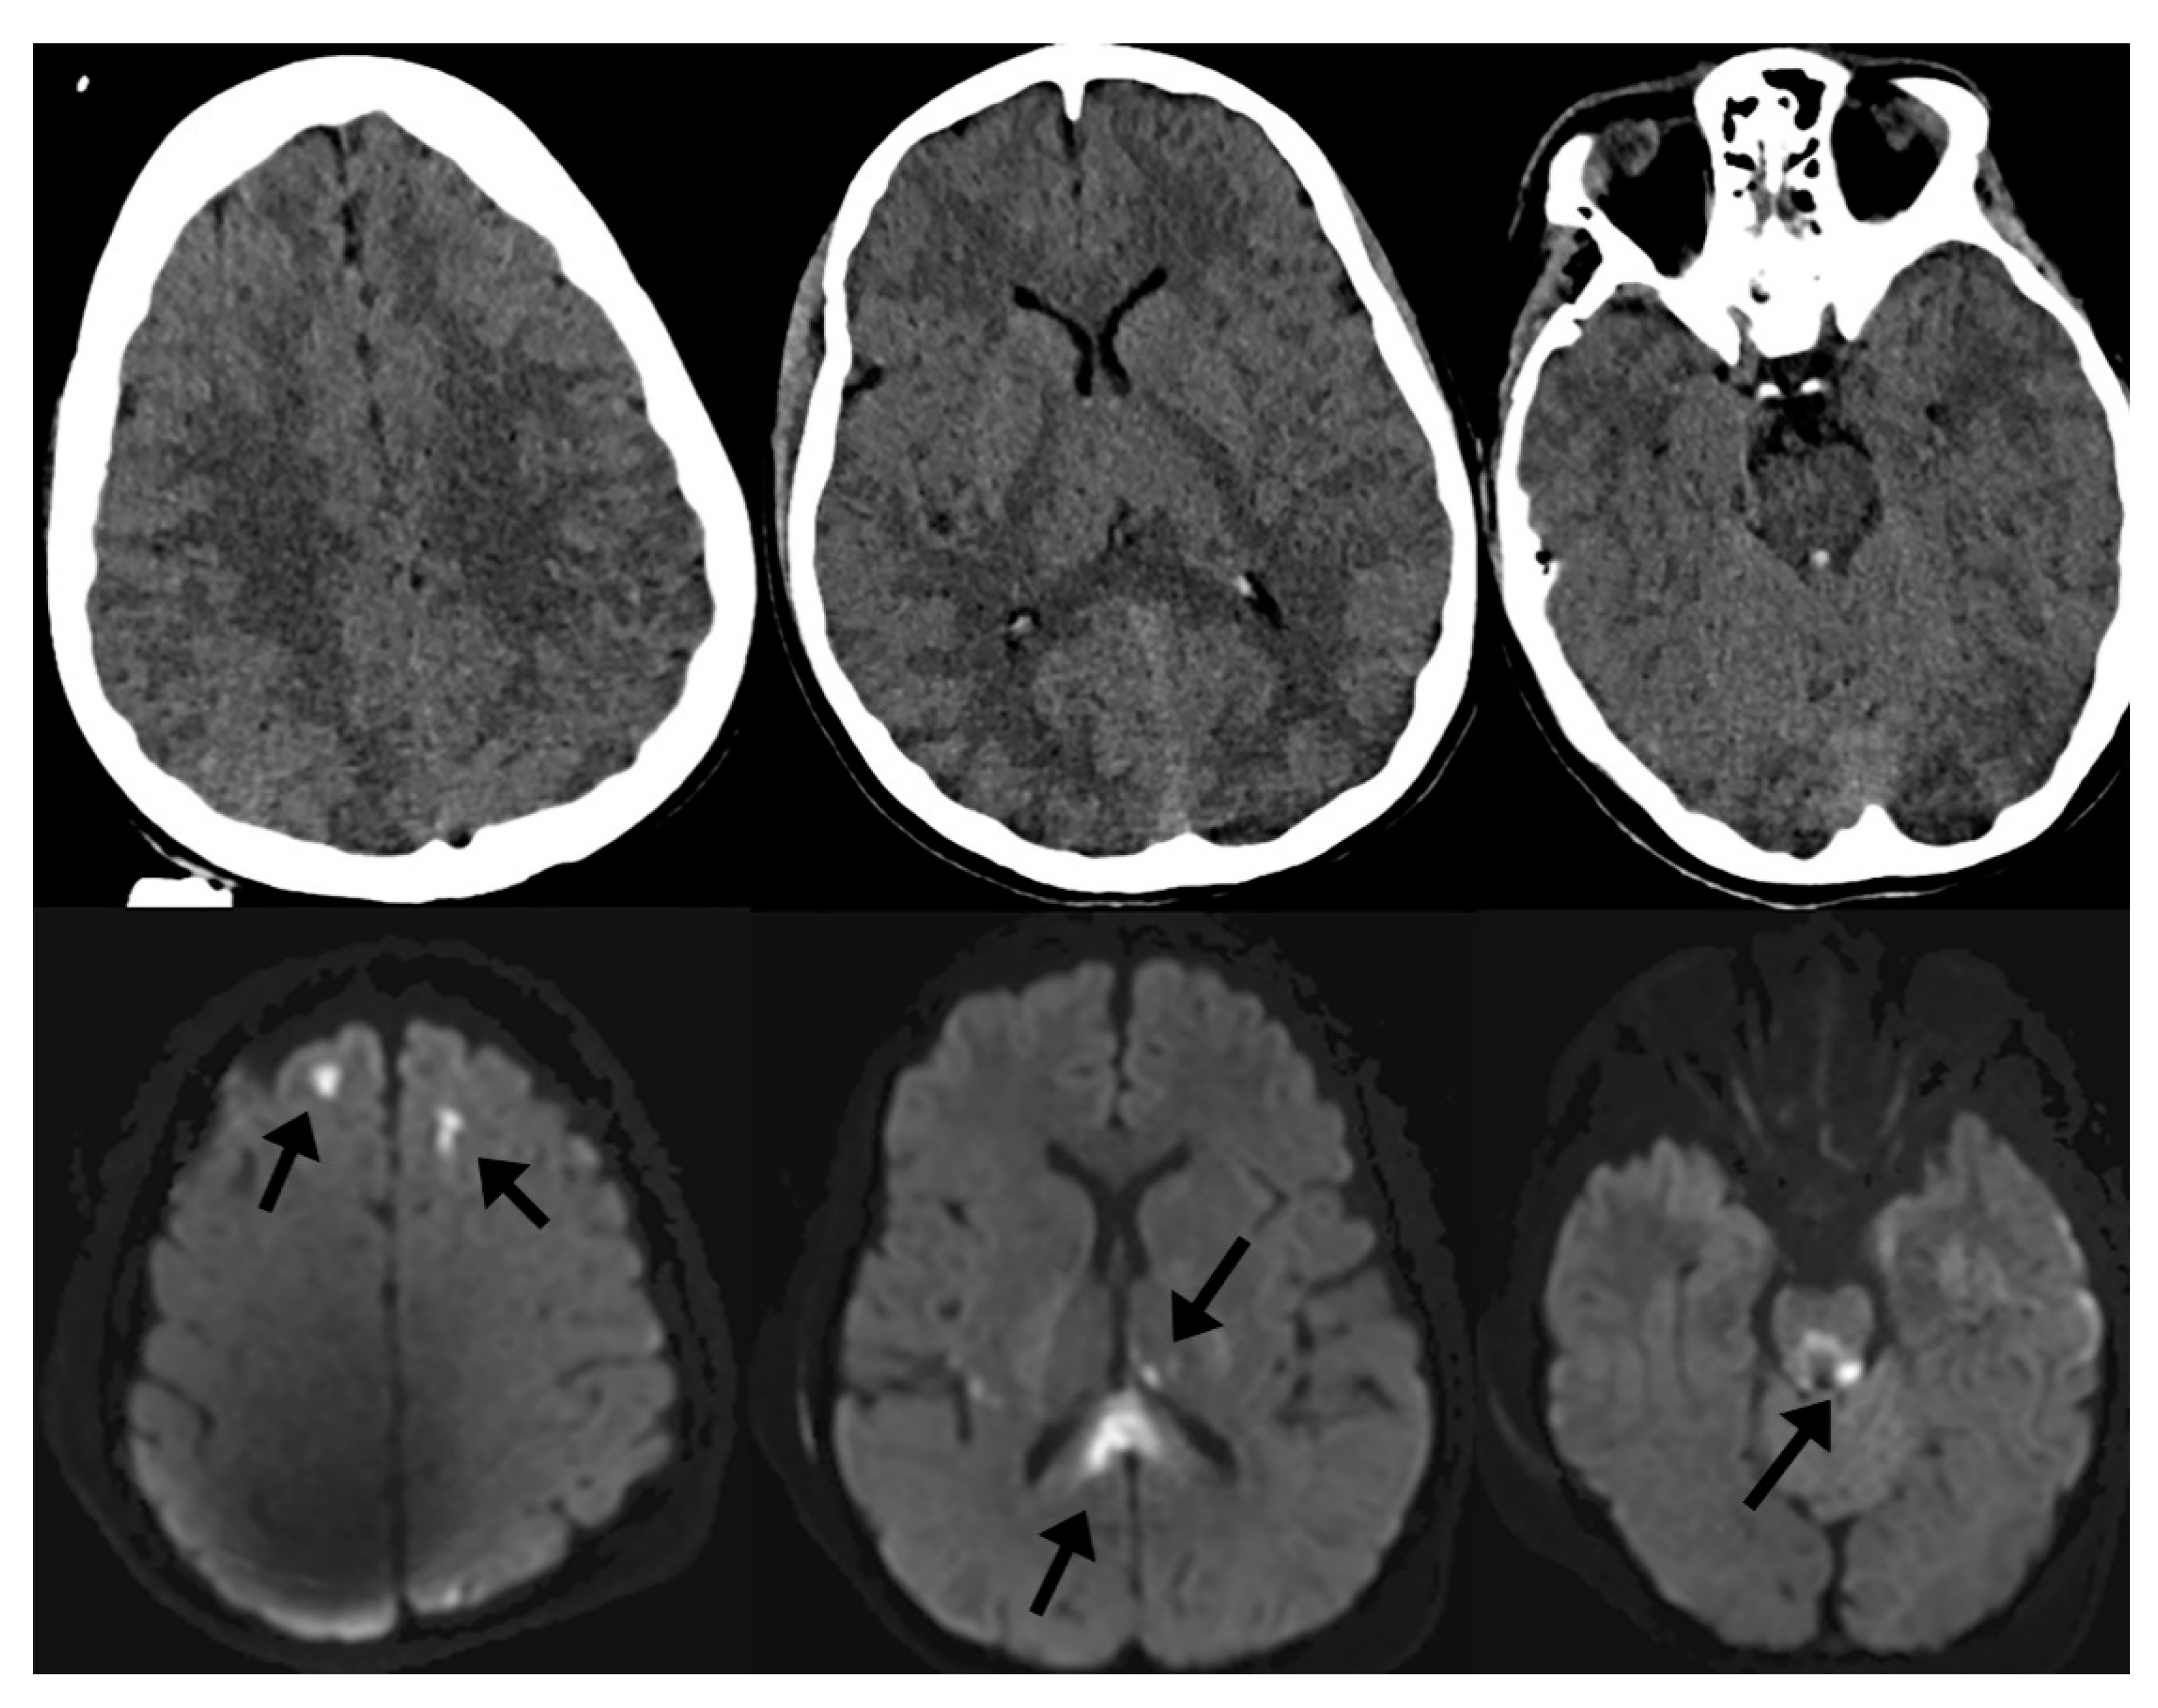

In the setting of TBI, specific conventional MRI sequences such as diffusion-weighted imaging (DWI) and susceptibility-weighted imaging (SWI) tend to be helpful in understanding the clinical implications of injury. In moderate-to-severe TBI, it is common to identify small, scattered microhemorrhages within the brain parenchyma after injury. These microhemorrhages, when localized to the gray–white junctions or white matter tracts, are associated with diffuse axonal injury (DAI). DAI has been extensively studied in the clinical—and less so the pathological—literature and is a negative prognostic factor in recovery from TBI [5,10,11,12,13,14,15,16,17,18]. Often, microhemorrhages related to shear injury are invisible on noncontrast CT because of limited tissue contrast with CT as well as dose reduction limitations in humans and associated noise. However, DWI and SWI sequences of MRI are sensitive enough to detect such small areas of cytotoxic edema and microhemorrhage and are high-sensitivity markers of DAI. Figure 1 demonstrates this phenomenon, where punctate microhemorrhages are difficult to visualize on head CT but are readily apparent on SWI. For this reason, MRI has become an important adjunctive imaging modality in cranial neurotrauma as a means to prognosticate on the expected cognitive and behavioral outcomes of patients [19].

Figure 1.

Noncontrast computed tomography (CT) of the head (top row) and diffusion-weighted imaging (DWI) of the brain (bottom row) of the same patient after traumatic brain injury (TBI). Imaging markers of diffuse axonal injury (DAI) include microhemorrhages on susceptibility-weighted imaging (SWI) as well as focal areas of cytotoxic edema on DWI (arrows) that are not visible on CT.